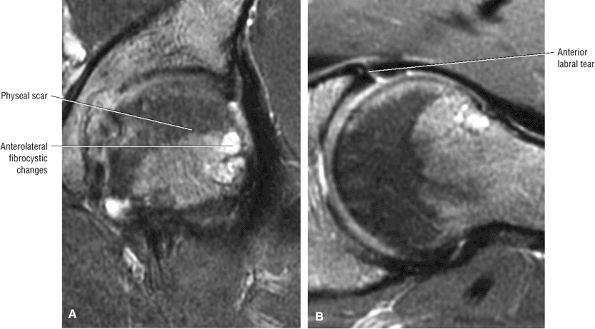

The femoral physeal scar is seen as a horizontal band of low signal intensity in an anterior-to-posterior orientation.

100 asymptomatic patients.53 In another study of renal transplant recipients, followed for 22 months using serial radiographs and MR, untreated AVN was shown to have a benign course without progression from Ficat stage 0.54 Jiang and Shih reported that the presence of a complete or dense physeal scar on MR scans was associated with a high risk for AVN of the femoral head.55 Segmental or incomplete scars in AVN were uncommon. The sealed-off or complete scar was shown to be a risk factor in patients with or without a history of steroid or alcohol abuse (associated lipogenic factors). Because it is possible to identify MR changes of focal osteonecrosis when radionuclide scans are negative and CT and plain film findings are normal,56 a limited or modified MR examination could be used as a low-cost screening tool in at-risk populations.

An enlarged or hypertrophied labrum may occur in patients with mild DDH.17 We have observed a femoral head chondral crease (Fig. 3.66) in these patients, creating a demarcation trough medial to a femoral head bump immediately proximal to the physeal scar. Patients who demonstrate femoroacetabular impingement (or lateral acetabular rim syndrome in DDH) also have direct impingement between the lateral acetabular labrum and the femoral head.